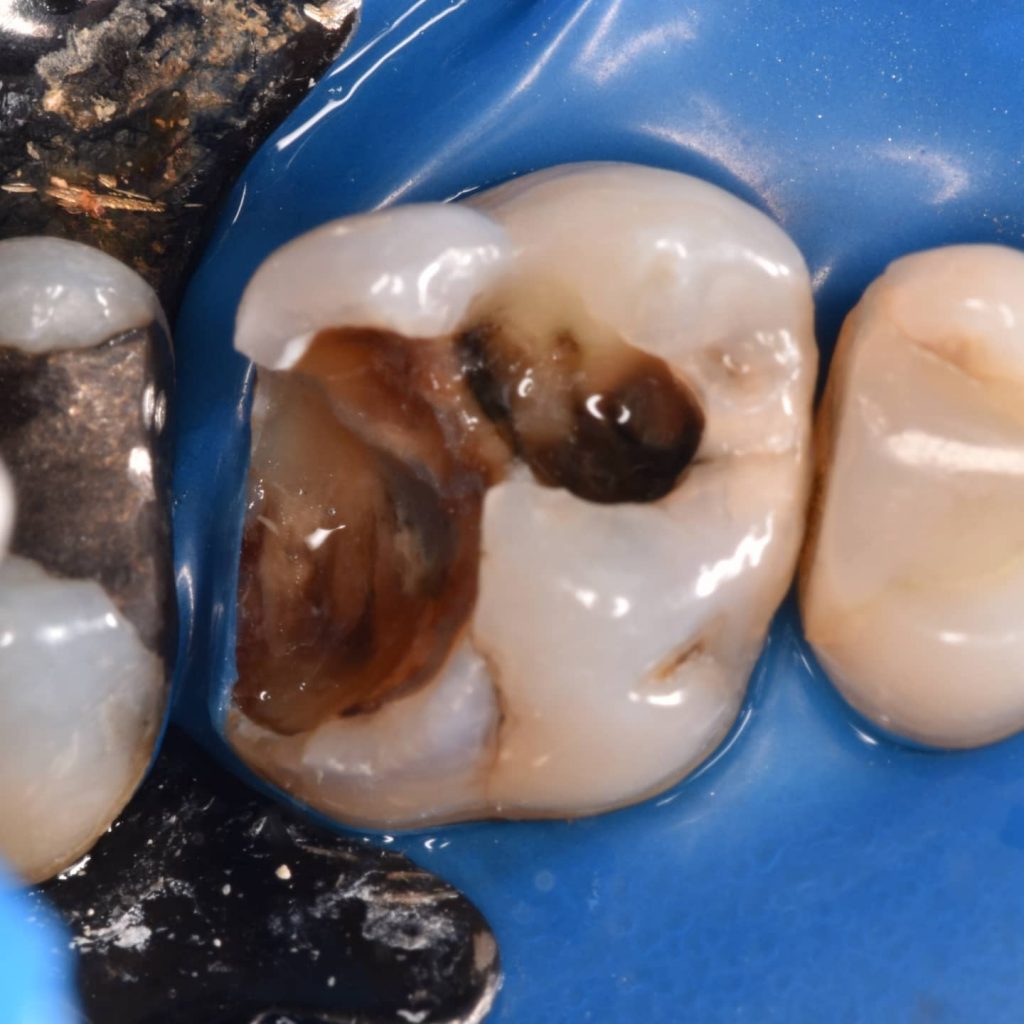

In cases of large cavity the choise of the type of restoration mostly go with indirect restoration(crown or onlay overlay ) when there is agreat loss of tooth structure to prevent fracture of the tooth and for long term treatment .

So when we can go with direct composite restoration in such cases ?

We can go with direct composite by using some materails that can prevent fracture and cracks and can save the tooth without going to indirect choise

This materails are (Ribond ,Ever X posterior …)els.

In this case I use the Ever X posterior wich is a fiber_reinforced composite for dentin replacement to support to the composite and give agood result that can withstand the occlusal forces .